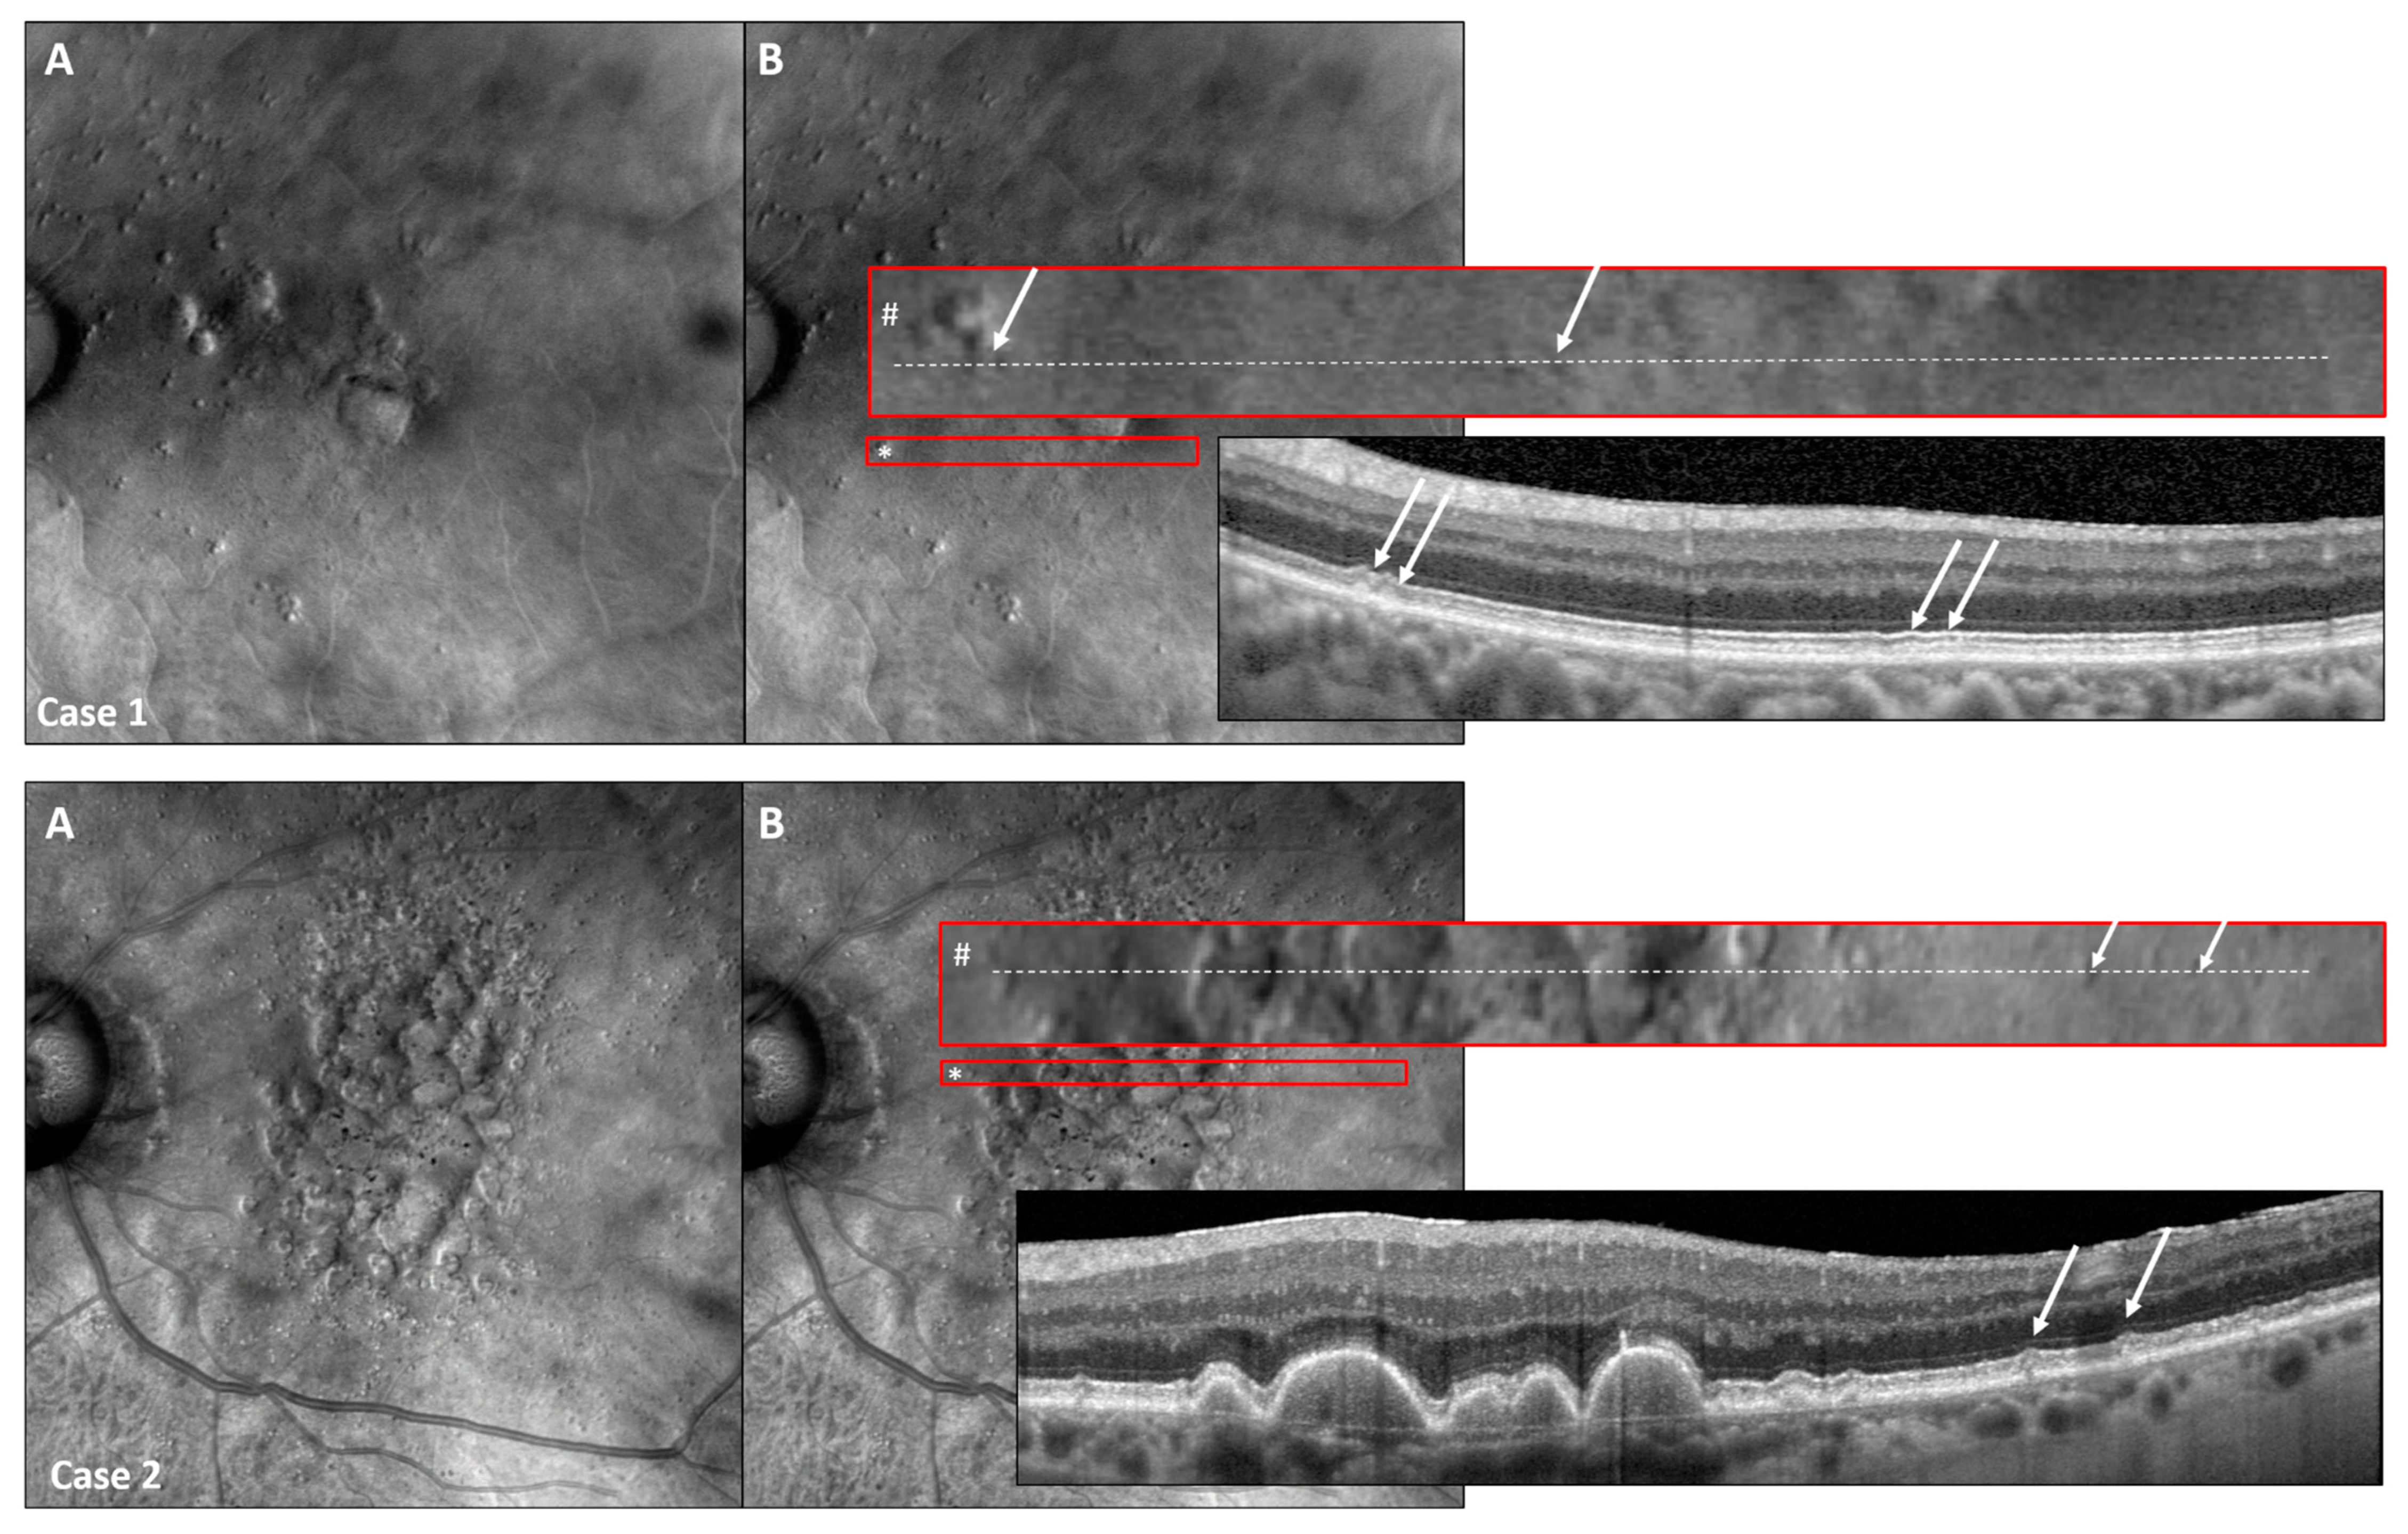

3.5. Retro Mode Detects Early Stages of SDDs